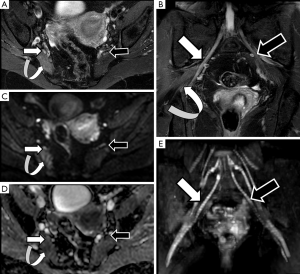

Brachial plexus roots and trunks on DTI after a direct or an indirect trauma demonstrate similar variations of FA or RD values to those described above for PN injuries. Neuropraxia of brachial plexus roots will show a decrease of FA values, due to loss of fiber organization, and increase of RD values (Figure 9). The amount of these changes is directly related to the severity of the neural damage and may be consider as a complementary tool to the clinical and electrophysiological evaluation (52).

Due to its deep location and complex anatomy, the evaluation of lumbosacral plexus by conventional ultrasound techniques or electrophysiological studies is very limited. MRI morphological and functional neurographic techniques have demonstrated high accuracy for the evaluation of this anatomical area (53). The incidence of nerve root, trunks or PN injuries at the pelvic region is usually linked to peripartum or surgical (intraoperative or postoperative) related complications. Adnexal lesions, complicated prolonged partum or gravid uterine extrinsic compression may also induce lumbosacral roots injuries, particularly involving the sciatic nerve during its course above the sacral wings or the iliac crests (54). The sciatic nerve, due to its length and course is usually involved in peripartum trauma mainly by traction or extrinsic compression mechanisms (55). DWN studies may provide useful information about the nerve continuity and the presence of edematous changes, which can be quantified by ADC values. The most common lesion in these patients is neuropraxia, and treatment monitoring can be performed using DWN as a progressive normalization of signal intensity and decrease of ADC values will occur during the recovery of the normal nerve function (Figure 10). Pudendal nerve may also be involved in peripartum trauma, however, due to its small diameter is hardly identified by DWN or DTN techniques, playing a major role for its evaluation high resolution morphological sequences (56).

Derived parameters from DWN or DTN, such as ADC or FA, have proved its usefulness to identify the involved lumbar nerve roots in cases of lumbar pain (57,58). An increase in ADC and a significant decrease in FA of compressed nerve roots compared with contralateral ones are detected in cases of symptomatic lumbar disk disease. This increase of ADC values is secondary to the venous congestion and edema that occurs in both pre-ganglionic and ganglionic segments of nerve lumbar roots (41). The decrease of FA values is also related to a loss of fiber anisotropy (Figure 11). At this point, it is important to remember that normal preganglionic nerve roots usually show physiologically lower FA values than PN, probably due to the absence of a complete neural fiber structure. This data has to be taken into account when quantification is performed at this small nerve structure, avoiding false positive results in patients without nerve compression. This quantitative assessment shows potential to form part shortly of the clinical lumbar spine MRI protocols as a tool to detect functional changes within the lumbar roots in patients with symptoms but without obvious disc protrusions (41).